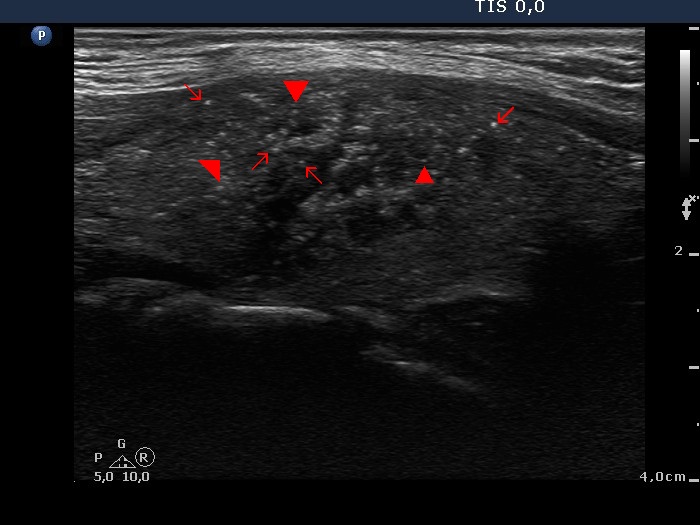

Papillary carcinoma (histological diagnosis) |

This case is less edifying or may be more edifying. Compared with the previous case, the granules here are less bright. Nevertheless, great proportion of them belong to punctate echogenic foci (arrows). It is worth to compare these with non-specific granules (arrowheads). |